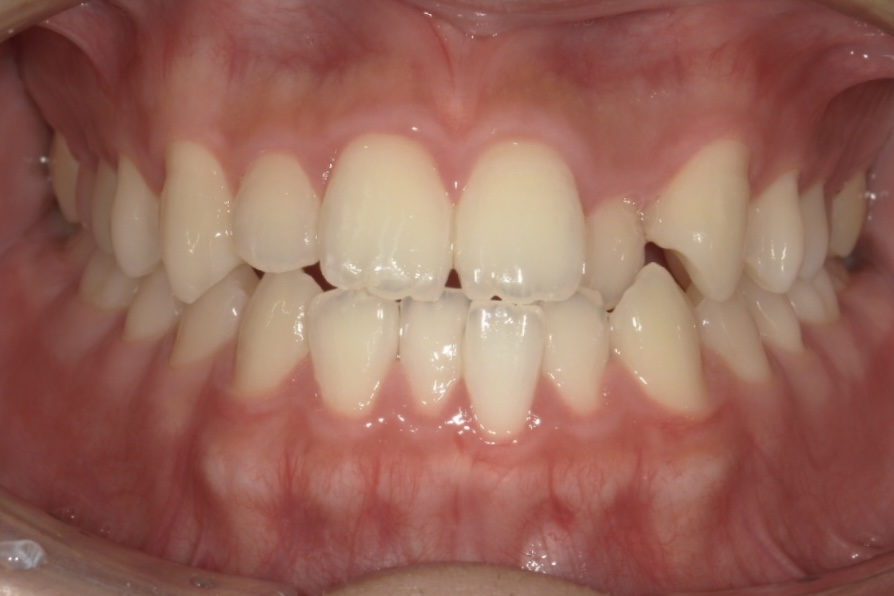

Before 3

After 3